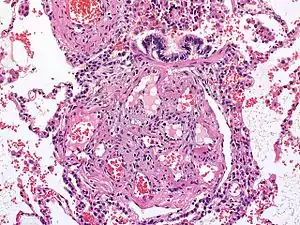

| در میکروگراف به علت هایپرتنسیون ریوی برگشت ناپذیر، ضایعه شبکهمانند در شش دیده میشود. رنگآمیزی اچای. | |